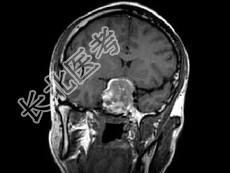

- 单项选择题男,26岁, 突发性视力障碍3天,根据所提供图像, 最可能的诊断为 ( )

D、嫌色细胞瘤(垂体瘤卒中)